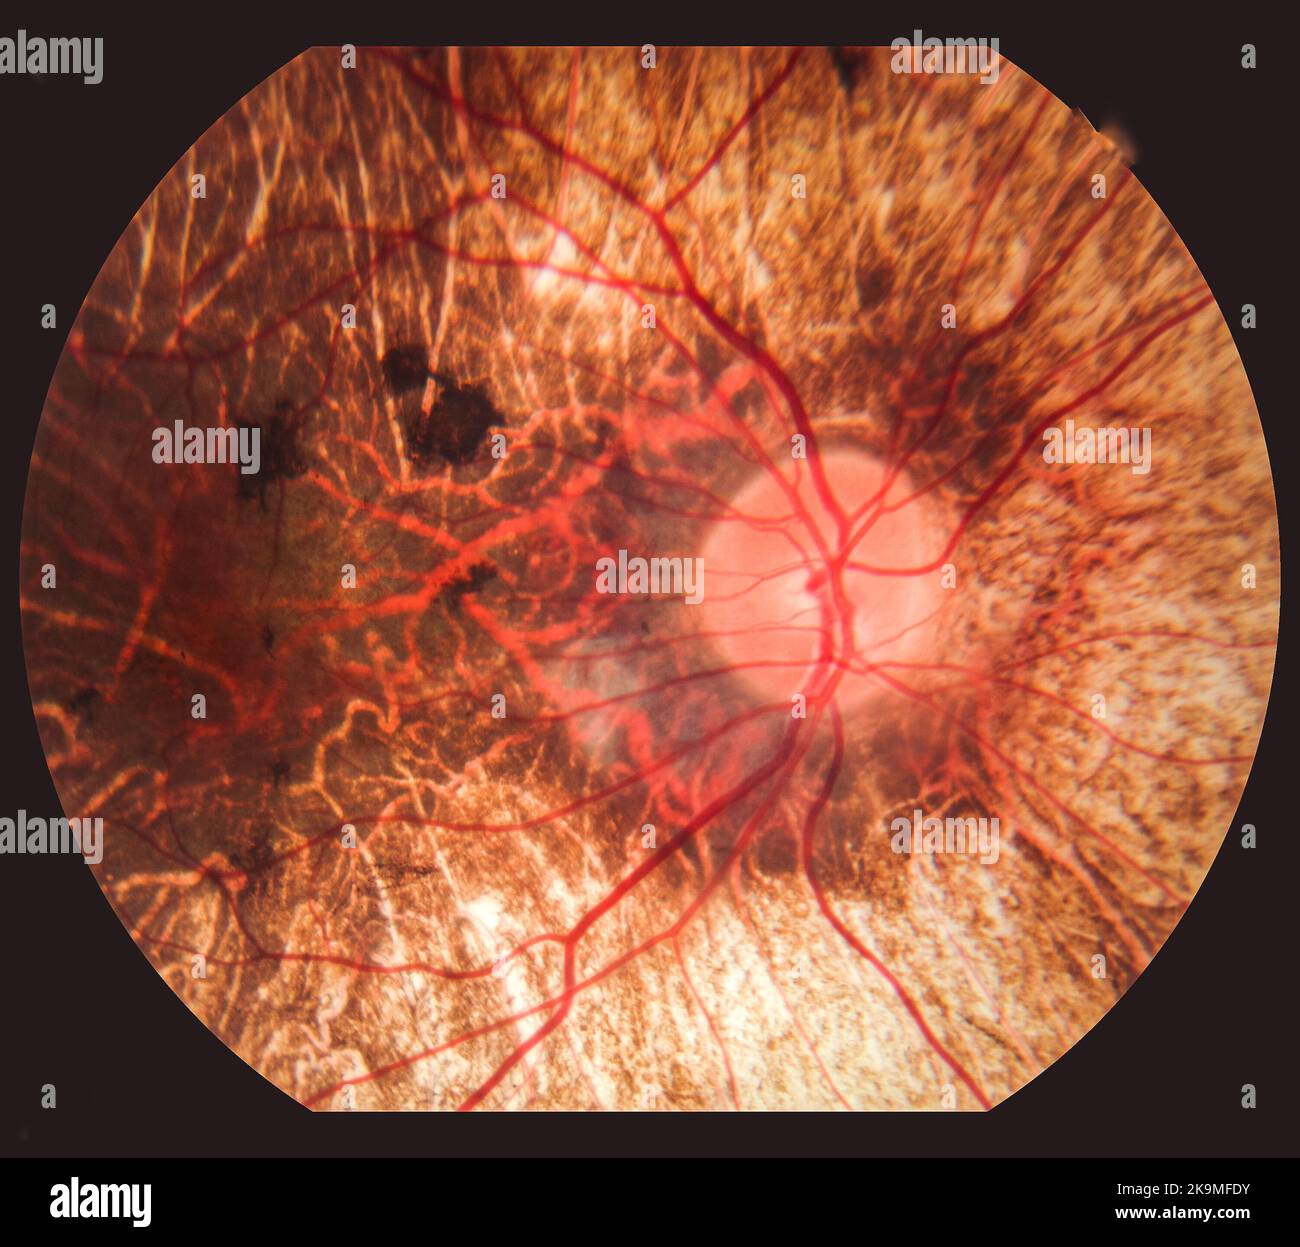

Fundus: routine examination established by an ophthalmoscope to check the health of the eye. Stock Photohttps://www.alamy.com/image-license-details/?v=1https://www.alamy.com/fundus-routine-examination-established-by-an-ophthalmoscope-to-check-the-health-of-the-eye-image476923031.html

Fundus: routine examination established by an ophthalmoscope to check the health of the eye. Stock Photohttps://www.alamy.com/image-license-details/?v=1https://www.alamy.com/fundus-routine-examination-established-by-an-ophthalmoscope-to-check-the-health-of-the-eye-image476923031.htmlRF2JKWM5B–Fundus: routine examination established by an ophthalmoscope to check the health of the eye.

Fundus of a patient with macular edema. Stock Photohttps://www.alamy.com/image-license-details/?v=1https://www.alamy.com/fundus-of-a-patient-with-macular-edema-image476923247.html

Fundus of a patient with macular edema. Stock Photohttps://www.alamy.com/image-license-details/?v=1https://www.alamy.com/fundus-of-a-patient-with-macular-edema-image476923247.htmlRF2JKWMD3–Fundus of a patient with macular edema.